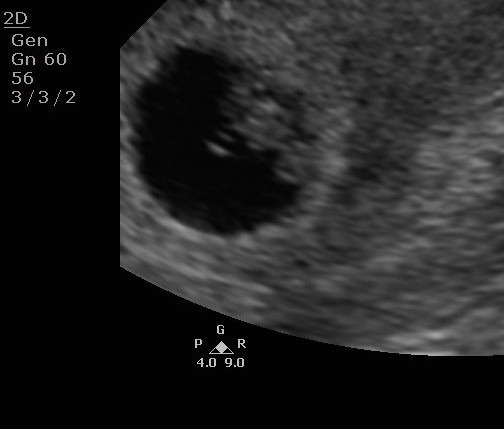

Couldn't confirm twins or singleton at 7wks?

I go back for a rescan in a week. Was wondering if anyone had anything similar or if this looks different? Thank you